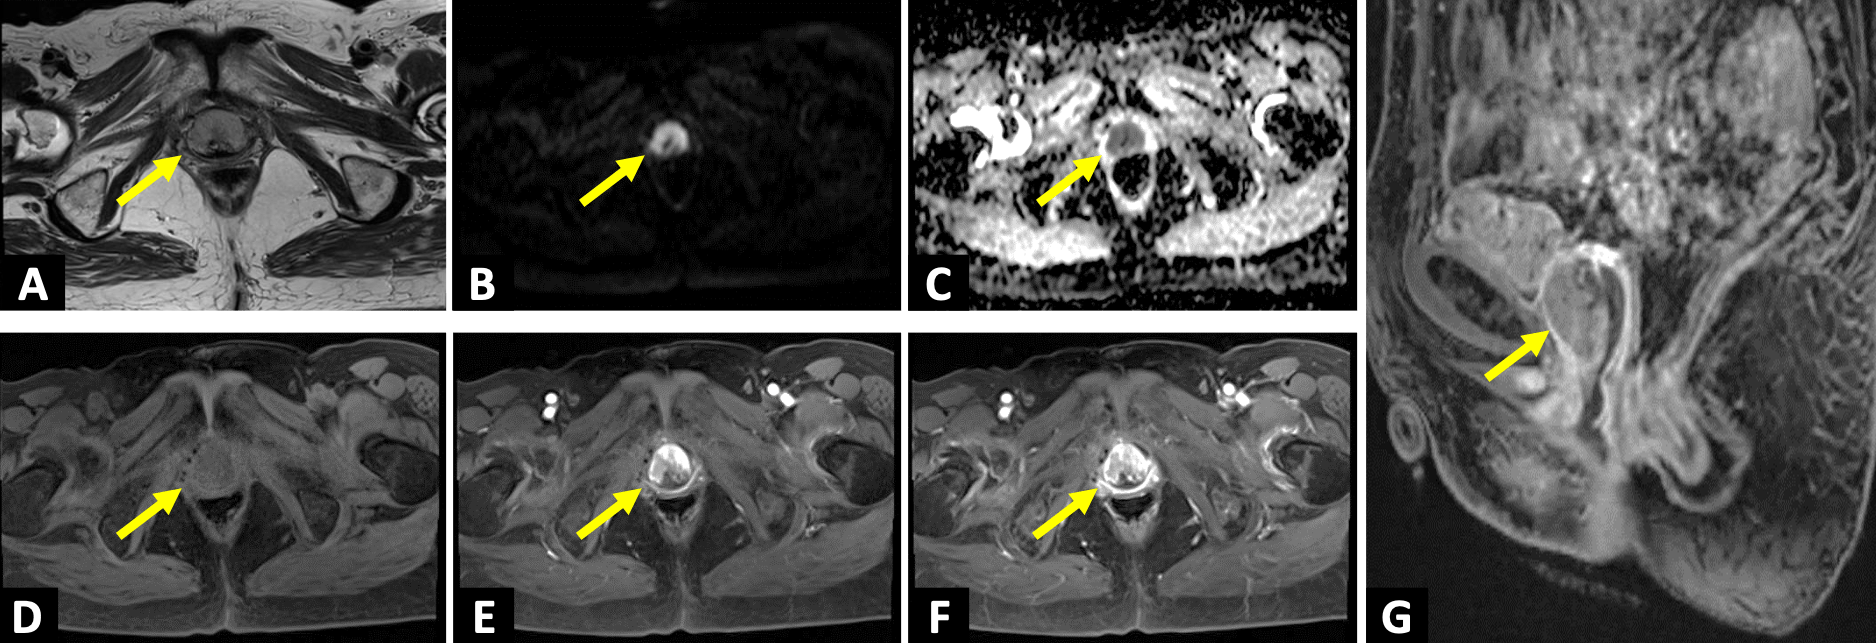

膀胱上皮内癌に対し膀胱全摘+回腸導管造設後。術後2年目に残存尿道から出血が出現したため造影CTを施行。尿道再発を疑う所見を認め、さらなる精査目的でガドビスト造影MRIを施行した。

症例解説

臨床および画像所見から、膀胱癌の尿道再発の術前診断のもと腫瘍切除が施行された。病理診断では、神経内分泌分化を伴う尿路上皮癌との結果であり、膀胱癌再発として矛盾しなかった。

本例では残存尿道に比較的粗大な腫瘤が形成されていたものの、CTでは若干所見が不明瞭であった。しかし、MRIを追加で撮像したことで病変を容易に検出することができた。骨盤内には複数の臓器が隣接して存在しているため、MRIの高いコントラスト分解能が診断に有用であった。なお、当施設には尿道専用のプロトコルが無かったため、今回の症例では前立腺のプロトコルを転用して撮像している。